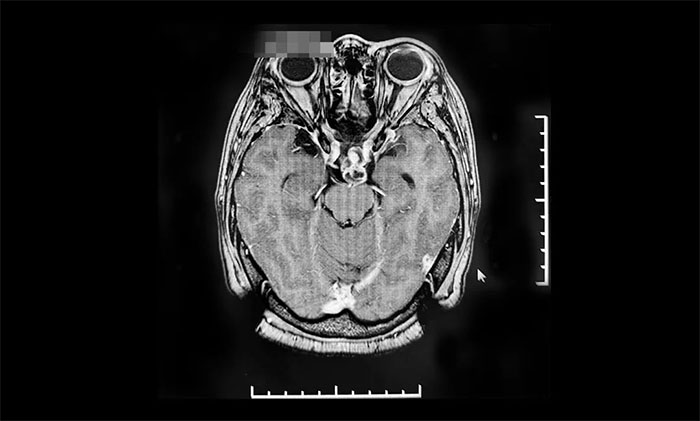

▲ 出院14個(gè)月后復(fù)查影像

2022年8月,因視力下降就醫(yī),復(fù)查提示腫瘤復(fù)發(fā),遂來(lái)上海藍(lán)十字腦科醫(yī)院進(jìn)行伽瑪?shù)吨委,后順利出院。今?0月,患者來(lái)院復(fù)查,影像學(xué)檢查提示腫瘤體積較治療前明顯縮小,患者視力較前改善,控制良好,陳琦主任叮囑其繼續(xù)隨訪觀察。